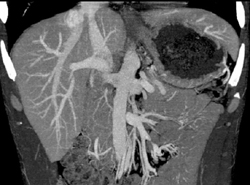

Islet Cell Involves the Portal Vein With Collaterals